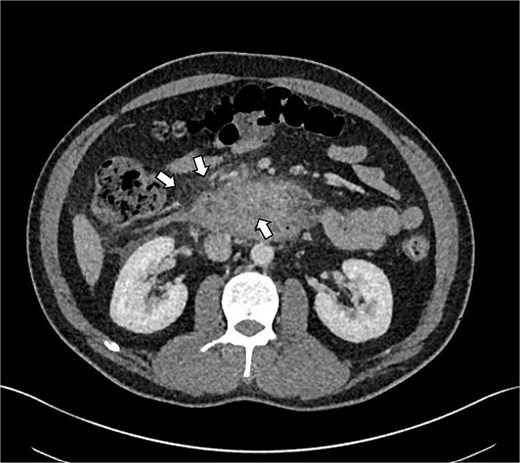

Abdominal and computed tomography of the abdomen and the pelvis (CTAP) showed oedematous change in the pancreatic head, uncinate process and also featured peripancreatic fat stranding which was deepened into the anterior pararenal spaces which were mostly right sided. There were no focal necrosis and homogeneous enhancement in the pancreas. Additionally, there was prominent reactive mesenteric lymphadenopathy and mucosal oedema in the second and third parts of the duodenum, likely reactive in nature (Fig. 1).

Shows axial CT scan showing prominent reactive mesenteric lymphadenopathy and mucosal oedema in the second and third parts of the duodenum (indicated by arrows), consistent with reactive inflammation in GP.

GP was differentiated from pancreatic adenocarcinoma by the presence of a relatively smooth, well-defined inflammatory mass in the pancreaticoduodenal groove, with less aggressive ductal distortion and absence of clear vascular encasement on contrast-enhanced computed tomography (CT). MRCP demonstrated groove-localized inflammation and duodenitis without a focally enhancing mass or typical ‘double-duct’ sign suggestive of pancreatic head malignancy (Figs 1–3).